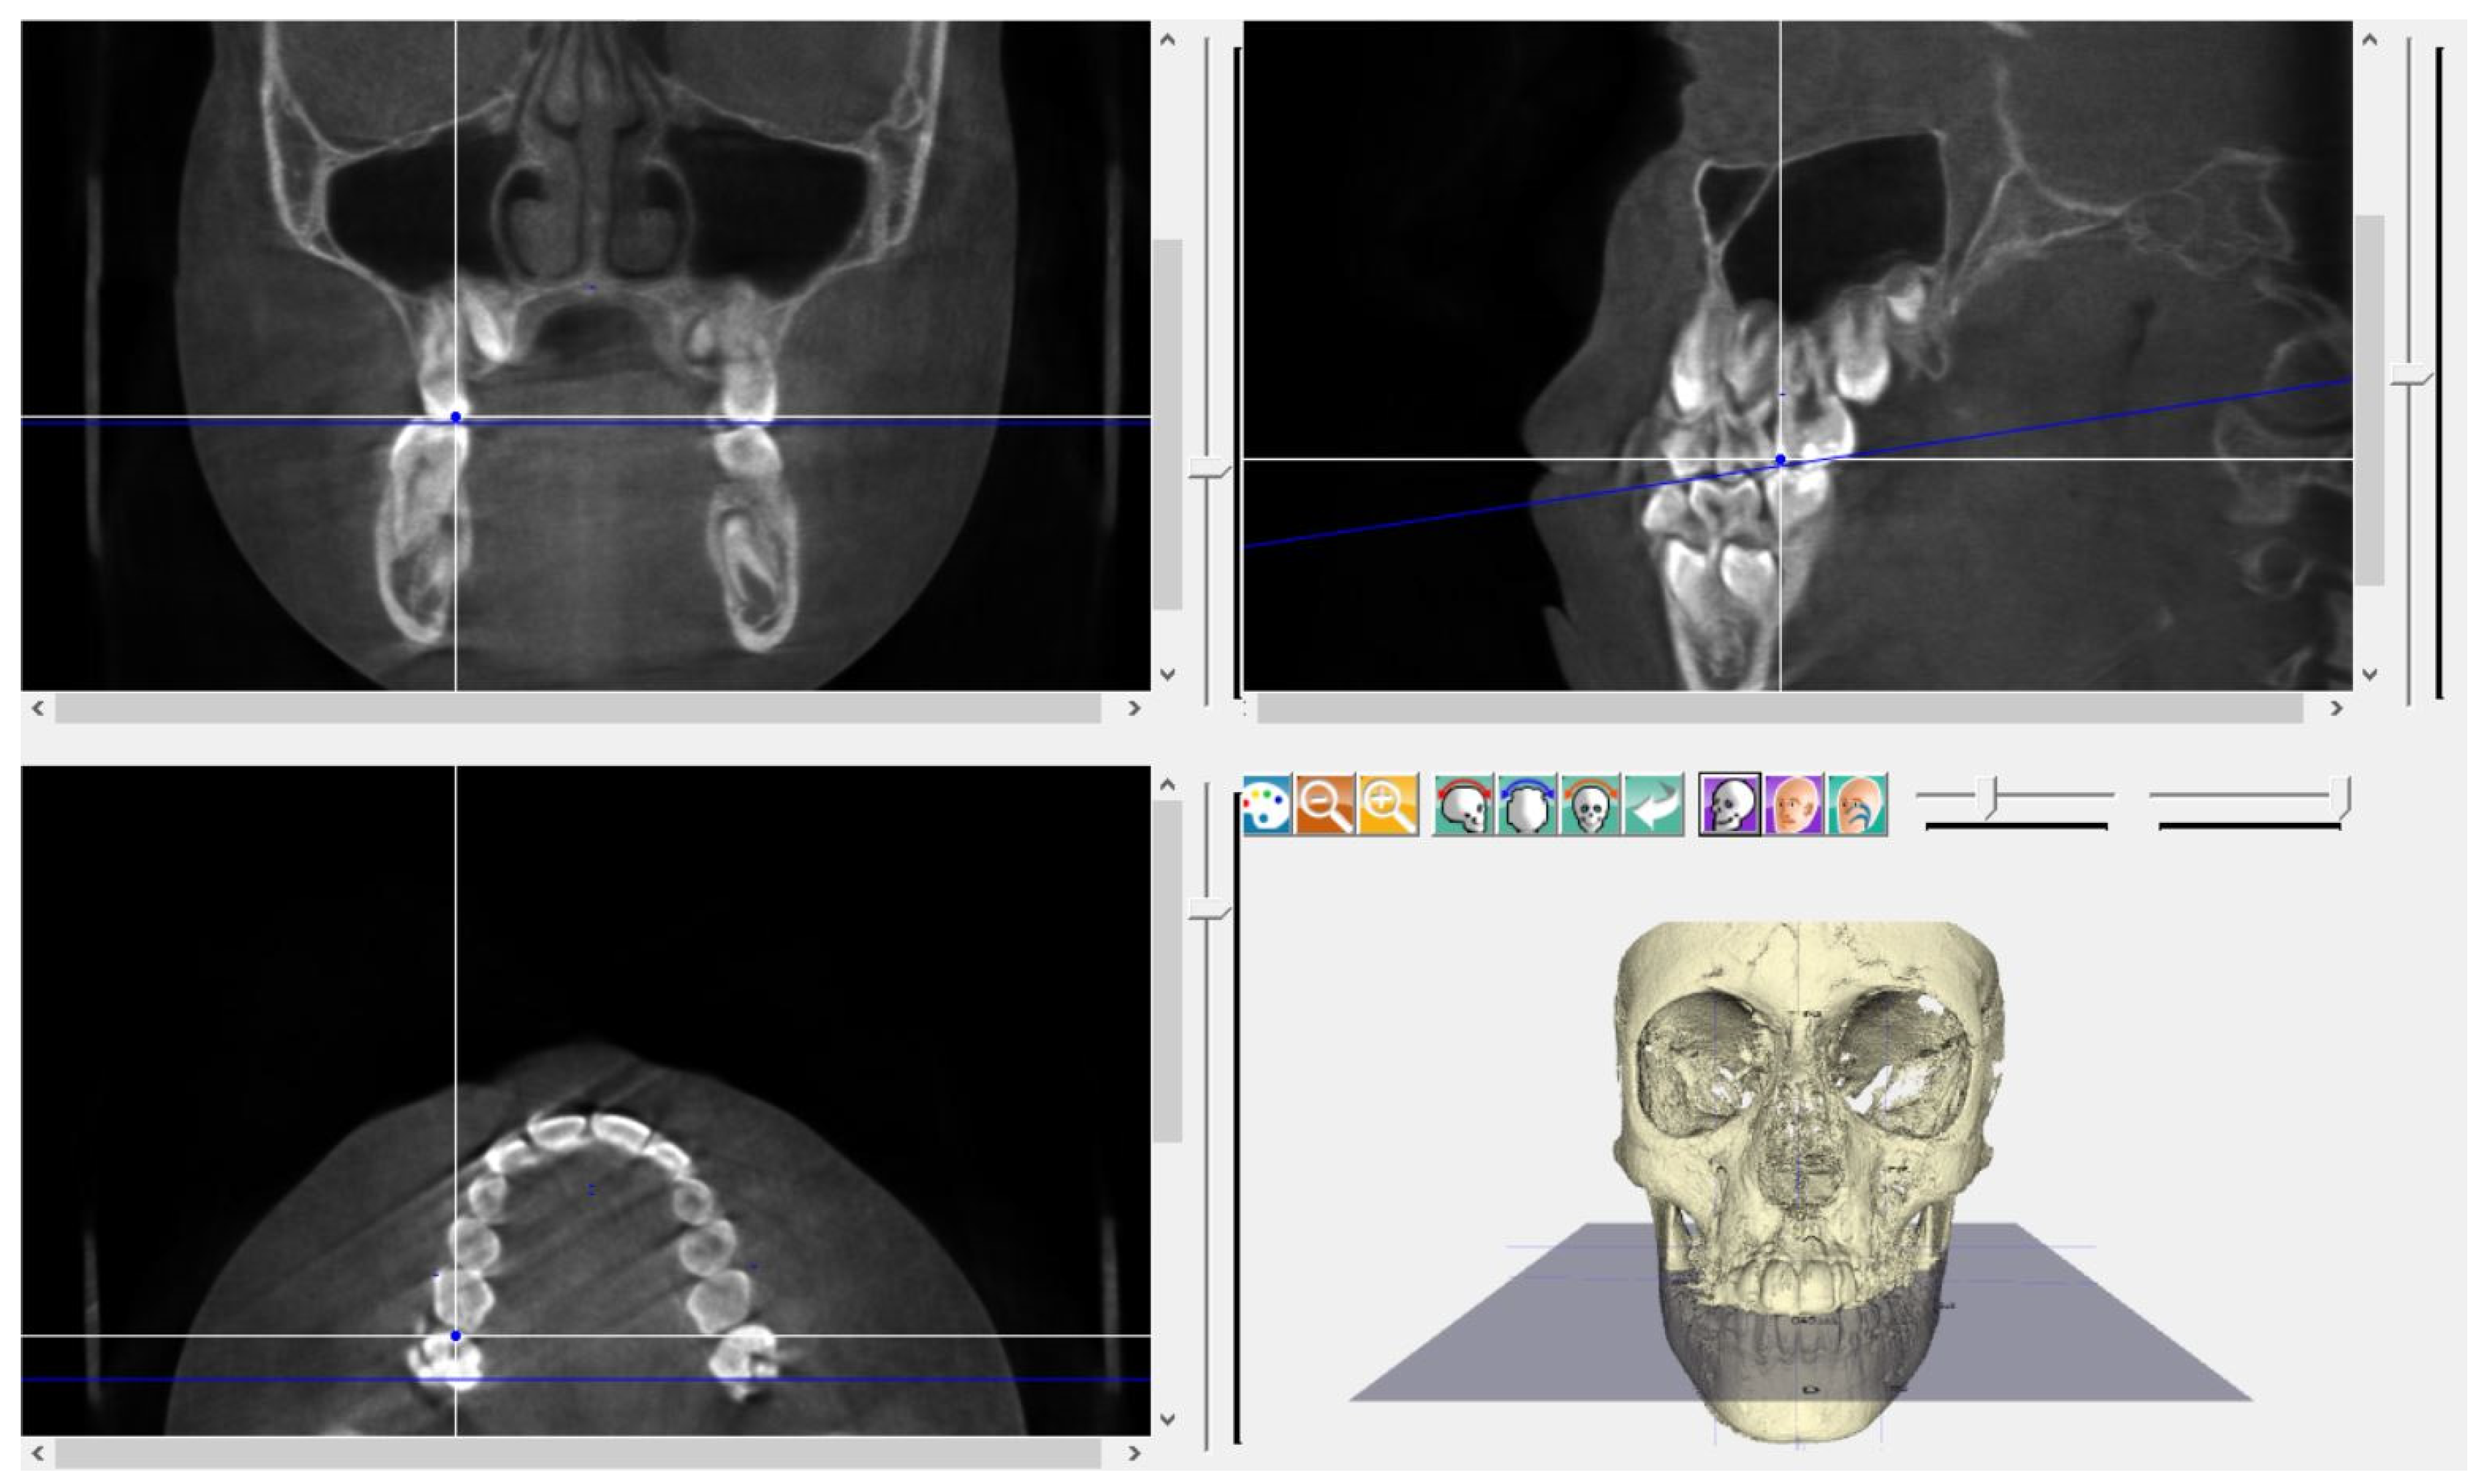

2. Materials and Methods